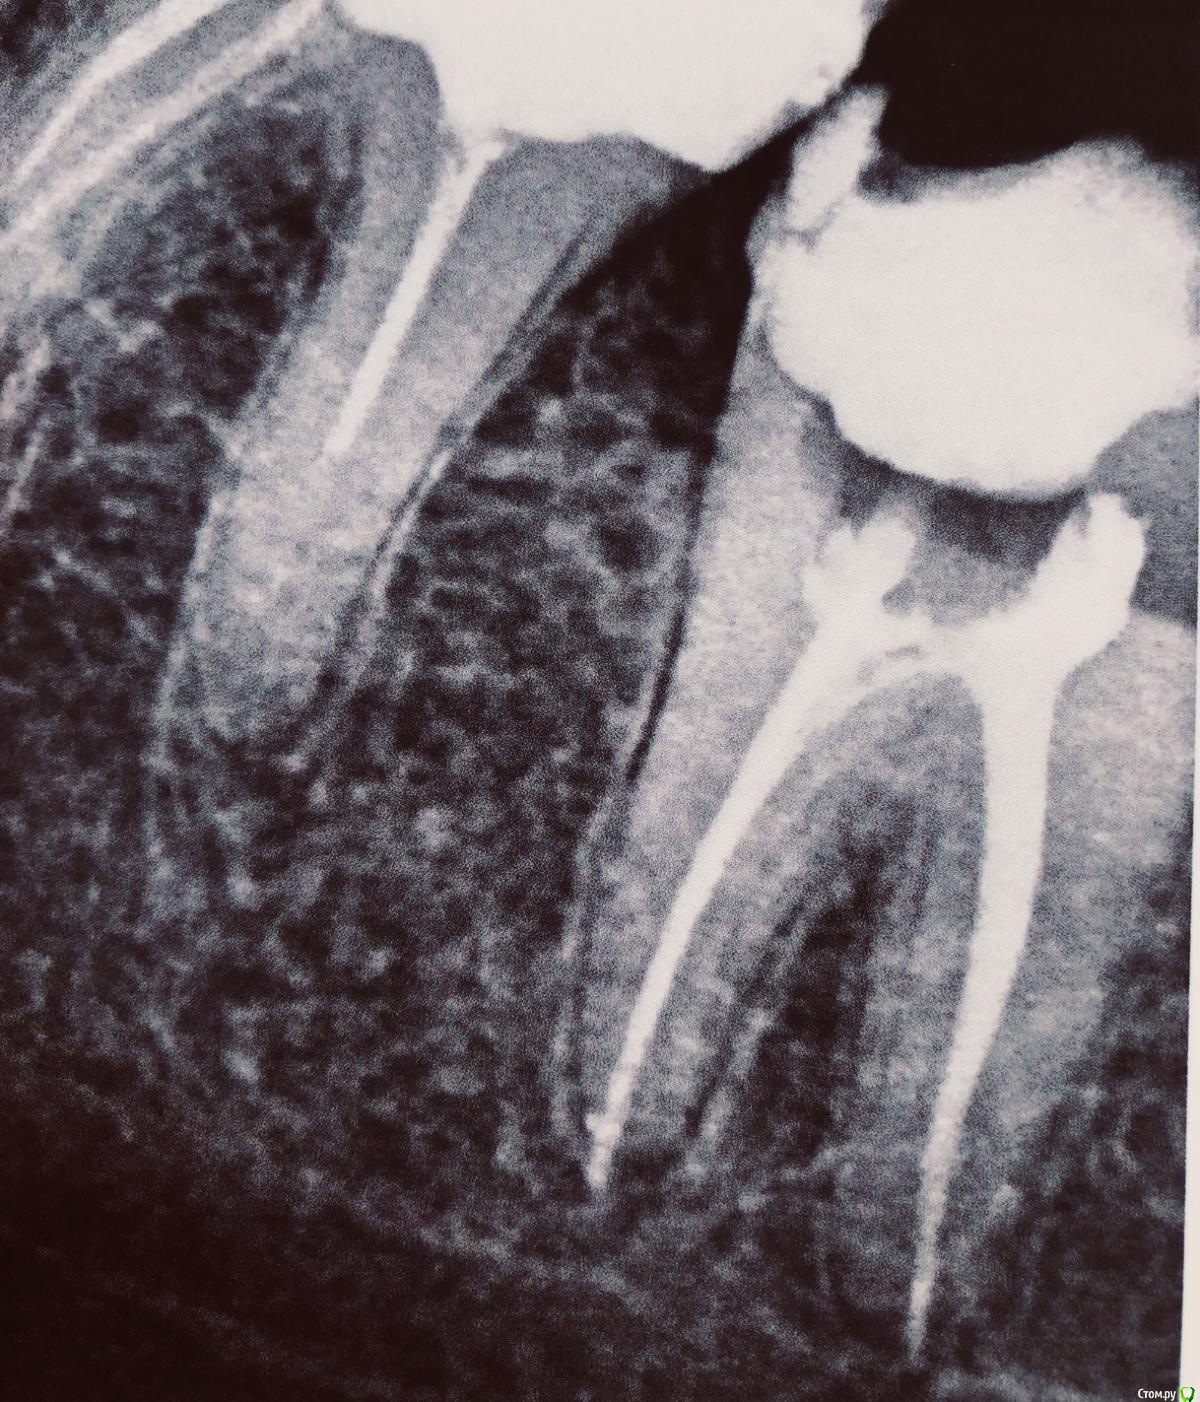

GalinaE Опубликовано 16 сентября, 2020 Автор Поделиться Опубликовано 16 сентября, 2020 (изменено) Снимок после лечения37 Изменено 16 сентября, 2020 пользователем GalinaE Ссылка на комментарий

GalinaE Опубликовано 16 сентября, 2020 Автор Поделиться Опубликовано 16 сентября, 2020 (изменено) Вот снова под вечер зуб разболелся. 6й день... Ну что это может быть?(((По снимку должно быть видно, нет ли перфорации? Я уже просто не знаю, на что думать Изменено 16 сентября, 2020 пользователем GalinaE Ссылка на комментарий

GalinaE Опубликовано 18 сентября, 2020 Автор Поделиться Опубликовано 18 сентября, 2020 Вот ещё снимки! Подскажите, пожалуйста, что это может быть? Ночью снова не спала толком от боли( Ссылка на комментарий